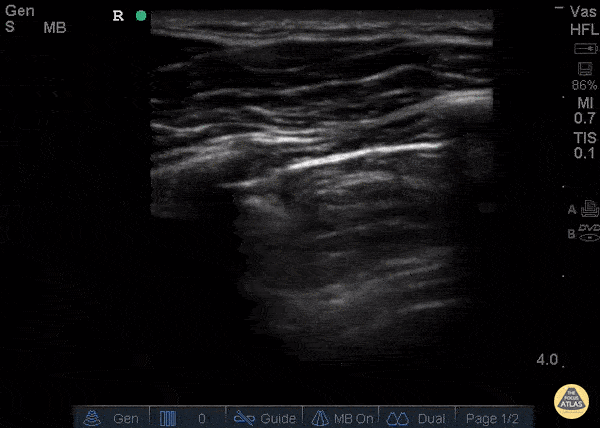

Pulmonary - Decreased Lung Slide - Pneumothorax

26 yo male presents to ED stating he was kicked in the chest. He went home to “try to relax and smoke some weed” now short of breath and with pleuritic chest pain after smoking. POCUS demonstrating decreased lung slide on the left. What are the signs of pneumothorax on ultrasound? Decreased lung sliding - In normal lungs, lung sliding refers to the parietal pleura moving against the visceral pleura - described as “ants marching.” Lack of B-lines or comet tails – These artifacts will not be present if there is a pneumothorax and the presence of B-lines or comet tails can rule out a pneumothorax. No Lung pulse – the visceral pleura moving along a stationary parietal pleura due to cardiac motion when lung sliding is not present. These are so called “T lines” on M-mode. These signify that the parietal and visceral pleura are opposing one another and therefore that there is no pneumothorax Lung point – 100% specific for pneumothorax, this is the cutoff point above which you can appreciate the lung sliding and below which there is no lung sliding. The lung point is the pneumothorax border. Dr. Stacey Frisch, Dr. John F Kilpatrick - Kings County Emergency Medicine